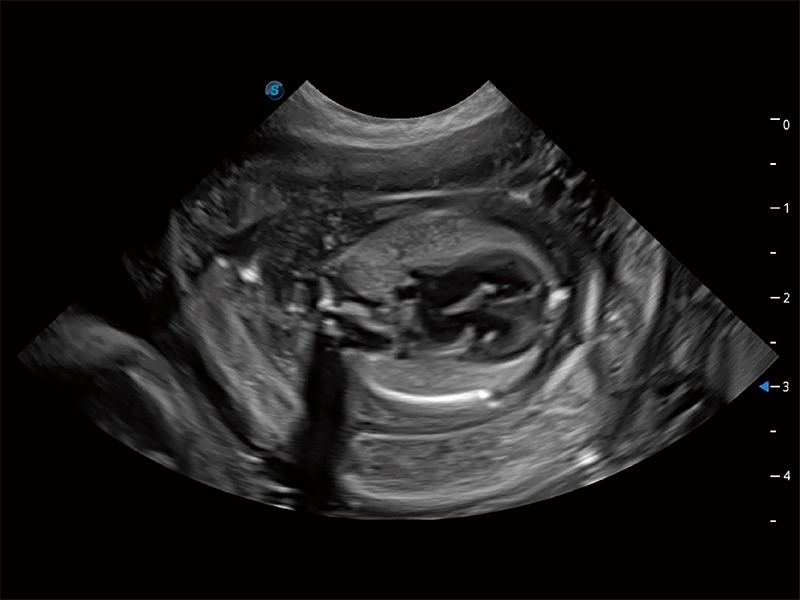

ProPet 80 专为动物医生设计,对不同的动物体型和生理结构作出了针对性的优化。通过动物影像专用软件,可满足个性化的应用需求,帮助动物医生获得更精确的诊断数据。

为精细结构及组织边缘提供高清晰度的图像和更大的成像视野。帮助减轻医生的用眼疲劳,快速精准获得测量的数据。